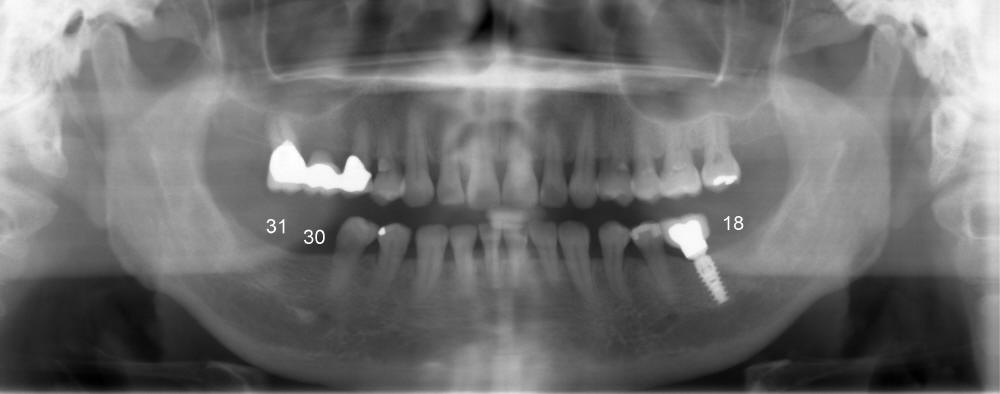

A 56-year-old lady requests implant placement at the sites of #18,30 and 31 (Fig.1, the last two first). CBCT shows preliminary design for implants at #30 and 31 (Fig.2 (sagittal section), 3,4 (coronal)).

One week postop, the gingiva buccal to #30 healing abutment was reddish (at the area indicated by arrowheads in Fig.10,11). The patient complained facial swelling. Clindamycin was taken one extra week to help resolve postop infection. By 24 days postop, there is no infection around these two healing abutments (Fig.10-12). The patient is pleased and makes an appointment for #18 implant placement (Fig.1), which is more challenging.